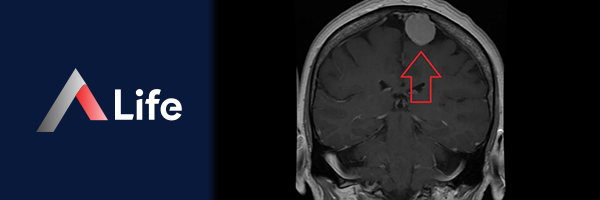

Menenjiom, beyni ve omuriliği çevreleyen zarlardan (meninksler) kaynaklanan, genellikle iyi huylu bir tümördür. Yavaş büyüyen bu tümörler, çoğu zaman hiçbir belirti göstermez ve rutin beyin görüntülemelerinde tesadüfen keşfedilir. Ancak bazı durumlarda, menenjiom büyüyerek beyne baskı yapabilir ve çeşitli nörolojik sorunlara yol açabilir.

• Manyetik Rezonans Görüntüleme (MR): Menenjiom teşhisinde en sık kullanılan görüntüleme yöntemidir. MR, beyin ve omuriliğin detaylı görüntülerini oluşturarak tümörün yerini, boyutunu ve çevre dokularla ilişkisini gösterir.

menenjiom_mr_g__r__nt__s______e6ddc523.webp